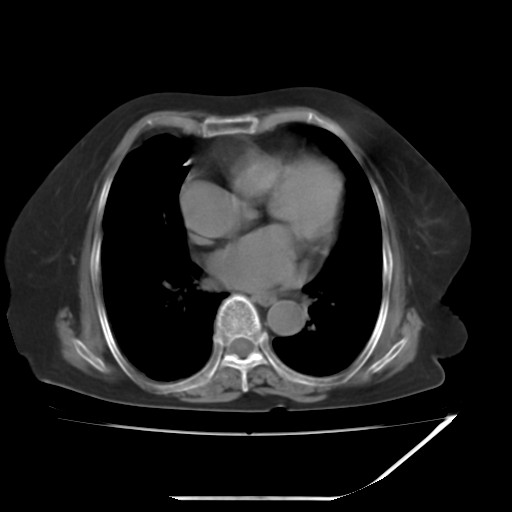

CT49699:腹部2天

麻烦各位老师帮我看一下,谢谢!·

胆囊炎、双肾体积稍小,请结合临床。

双肾似有缩小

双肾似有缩小,胸廓呈桶状,请结合临床

未见明显异常